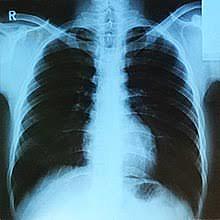

• X-rays

X-rays

Wilhelm Rontgen discover x-rays.